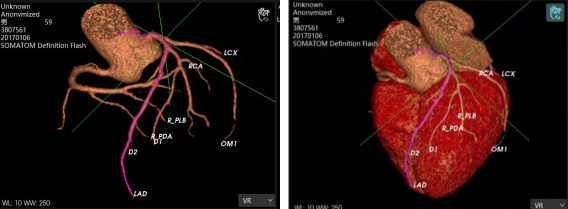

AI智能影像輔助診斷技術(shù)具有對醫(yī)學(xué)影像進(jìn)行圖像篩查、病灶分類、定位、檢測、圖像分割等優(yōu)勢。它能夠在海量的醫(yī)學(xué)影像中準(zhǔn)確、快速且客觀地篩選出特定疾病的影像,確定圖像中病變區(qū)域的空間位置,檢測需要識別圖像中所有的目標(biāo)并且確定其類別,并在醫(yī)學(xué)影像中分割標(biāo)注出不同的組織和器官,計(jì)算圖像中的血流量等代謝信息。

除上述肺結(jié)節(jié)人工智能篩查示例外,目前已形成了全鏈路人工智能產(chǎn)品解決方案,在影像、超聲、病理方面都與AI智能影像輔助診斷技術(shù)高效結(jié)合,幫助醫(yī)院實(shí)現(xiàn)自動化、高精度的影像診斷檢查,讓患者在疾病篩查中實(shí)現(xiàn)早期診斷、預(yù)測、治療、療效評估與監(jiān)測。